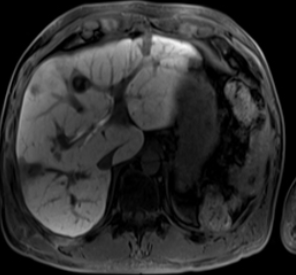

그리고 내년부터는 보장성강화를 위해 건강보험공단에서 복부 및 다른 부위에도 MRI 적용을 위해 제도 개선을 실시 중이라고 합니다.